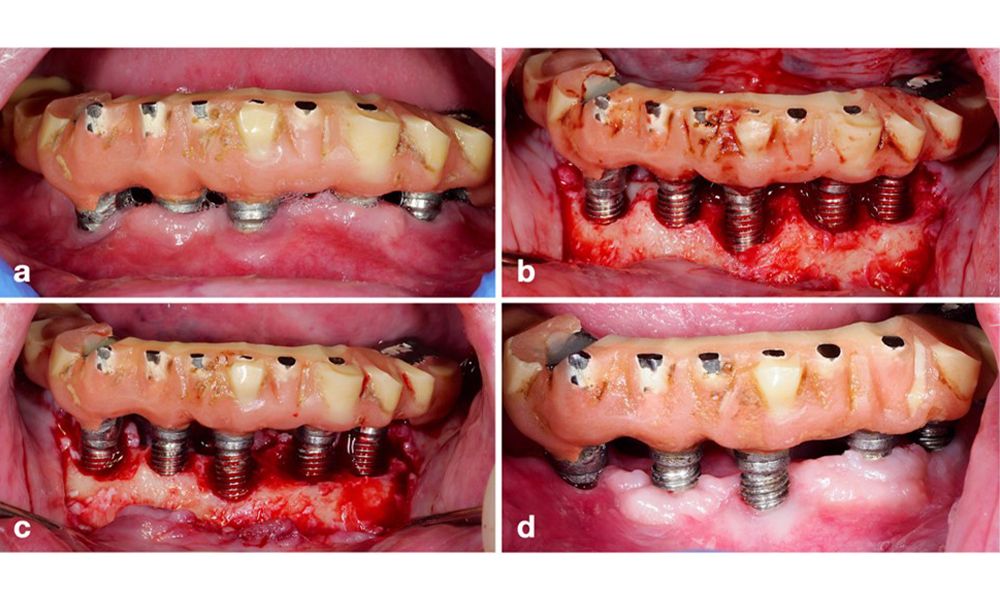

Defect extent, implant position, and its strategic importance determine whether an implant can or should be treated. Similar to a non-treatable (hopeless) implant, a severely affected implant in a multiple-unit restoration may be irrelevant for treatment, as its loss does not compromise the prosthetic restoration. Consequently, it is advisable to consider explantation either upon diagnosis or during surgical intervention (figure 8).

Explantation of a severely affected implant using a piezo surgery device. The implant in position 43 was part of a 4-unit bridge supported by 3 implants. Because of significant bone loss and minor relevance in the support for the bridge, treating the implant was deemed impractical. Explantation was performed with a piezo surgery device and specially designed tips (a-c) ensuring a minimal amount of bone loss (d).

Figure 8. Explantation of a severely affected implant using a piezo surgery device. The implant in position 43 was part of a 4-unit bridge supported by 3 implants. Because of significant bone loss and minor relevance in the support for the bridge, treating the implant was deemed impractical. Explantation was performed with a piezo surgery device and specially designed tips (a-c) ensuring a minimal amount of bone loss (d).

A resective approach (i.e., gingivectomy and/or apically positioned flap, with/without bone re-contouring) should be chosen in cases with mainly horizontal bone loss or wide defects, where the potential for bone regeneration is limited (figure 11).

Patient treated with a resective approach (a). After flap elevation mainly horizontal bone loss is seen (b), addressed by bone re-contouring (c) and an apically displaced flap resulting in a stable post-operative result (d).

Figure 11. Patient treated with a resective approach (a). After flap elevation mainly horizontal bone loss is seen (b), addressed by bone re-contouring (c) and an apically displaced flap resulting in a stable post-operative result (d).